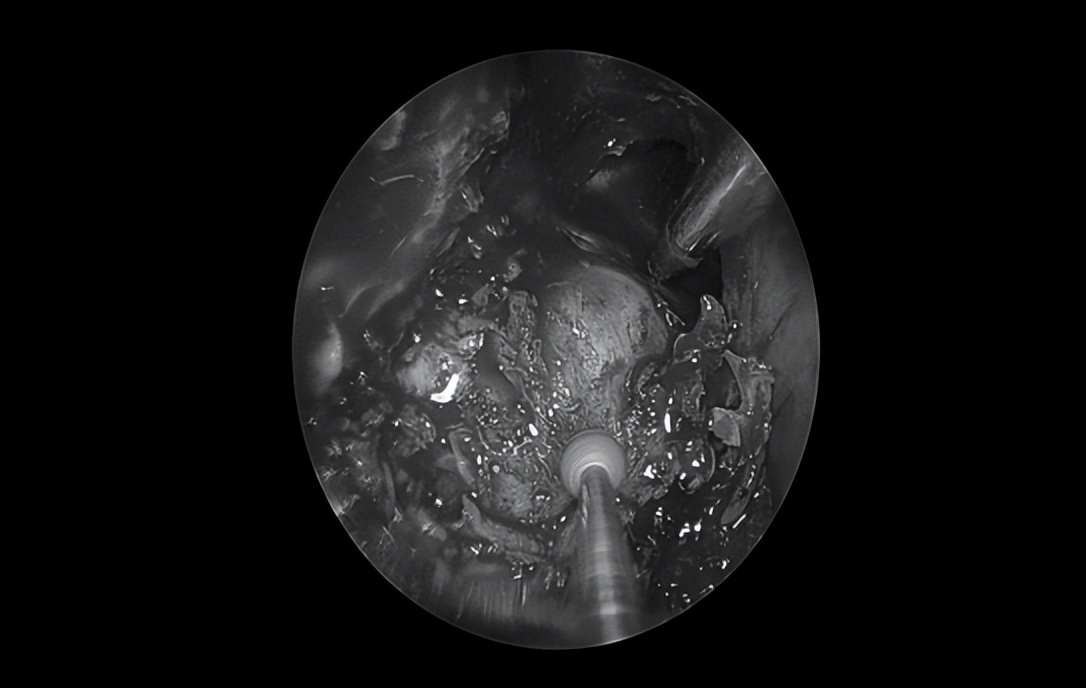

清除豆渣样物,显露岩骨段颈内动脉

清除囊内病变后可见中颅窝底塌陷

(星号标示处)

切除部分囊壁,清除囊内病变,充分向鼻腔开放引流